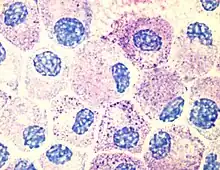

Most histamine in the body is generated in granules in mast cells and in white blood cells (leukocytes) called basophils. Mast cells are especially numerous at sites of potential injury – the nose, mouth, and feet, internal body surfaces, and blood vessels. Non-mast cell histamine is found in several tissues, including the hypothalamus region of the brain, where it functions as a neurotransmitter. Another important site of histamine storage and release is the enterochromaffin-like (ECL) cell of the stomach.

The most important pathophysiologic mechanism of mast cell and basophil histamine release is immunologic. These cells, if sensitized by IgE antibodies attached to their membranes, degranulate when exposed to the appropriate antigen. Certain amines and alkaloids, including such drugs as morphine, and curare alkaloids, can displace histamine in granules and cause its release. Antibiotics like polymyxin are also found to stimulate histamine release.

Mast cells serve an important immunological role by defending the body from antigens and maintaining homeostasis in the gut microbiome. They act as an alarm to trigger inflammatory responses by the immune system. Their presence in the digestive system enables them to serve as an early barrier to pathogens entering the body. People who suffer from widespread sensitivities and allergic reactions may have mast cell activation syndrome (MCAS), in which excessive amounts of histamine are released from mast cells, and cannot be properly degraded. The abnormal release of histamine can be caused by either dysfunctional internal signals from defective mast cells or by the development of clonal mast cell populations through mutations occurring in the tyrosine kinase Kit.[21] In such cases, the body may not be able to produce sufficient degradative enzymes to properly eliminate the excess histamine. Since MCAS is symptomatically characterized as such a broad disorder, it is difficult to diagnose and can be mislabeled as a variety of diseases, including irritable bowel syndrome and fibromyalgia.[21]